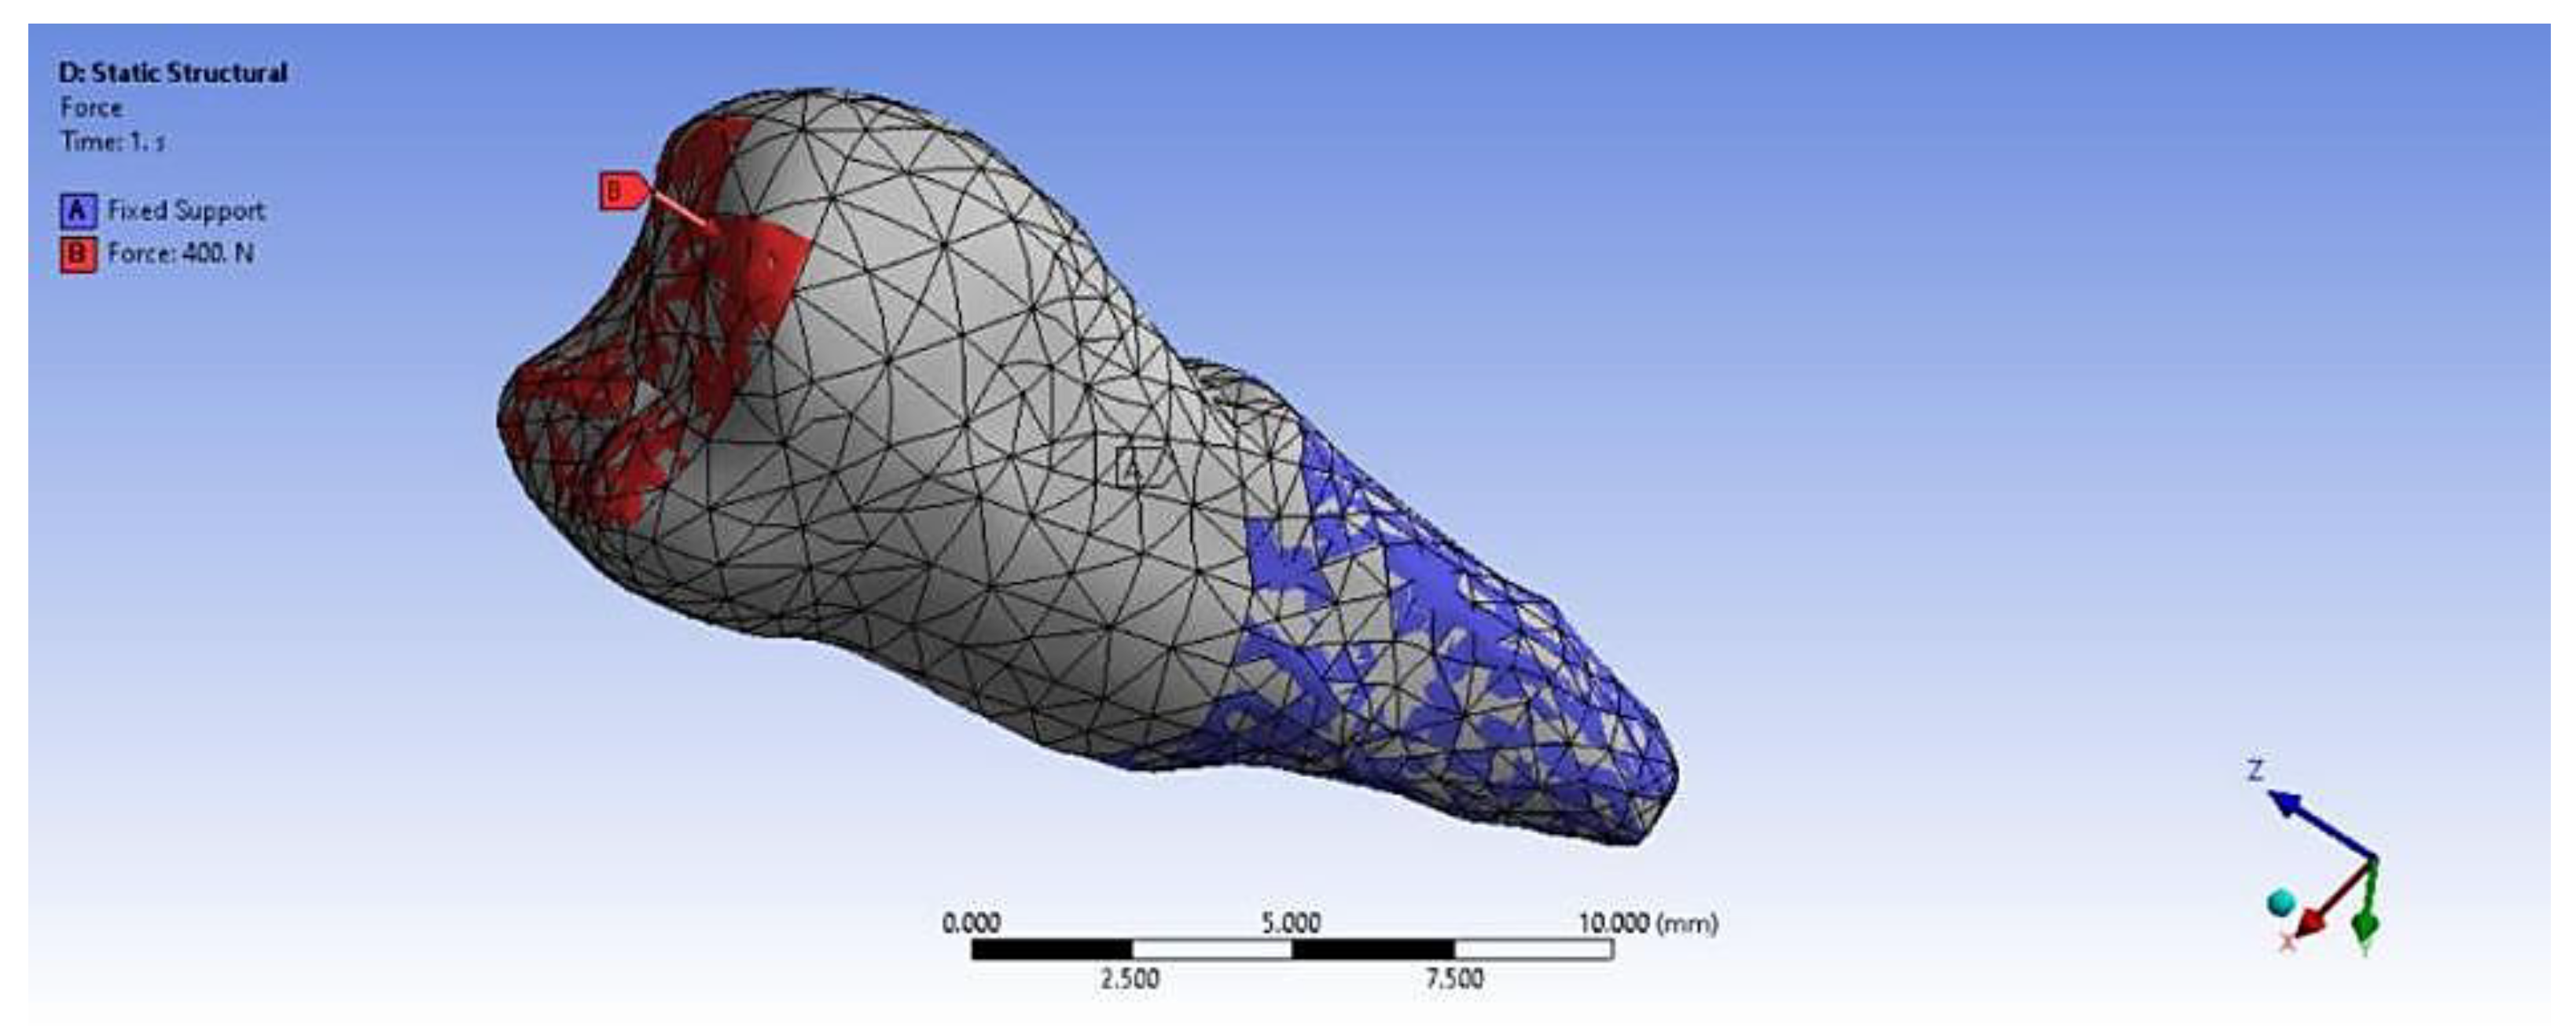

3. Finite Element Analysis (FEA) of Mandibular Right Premolars